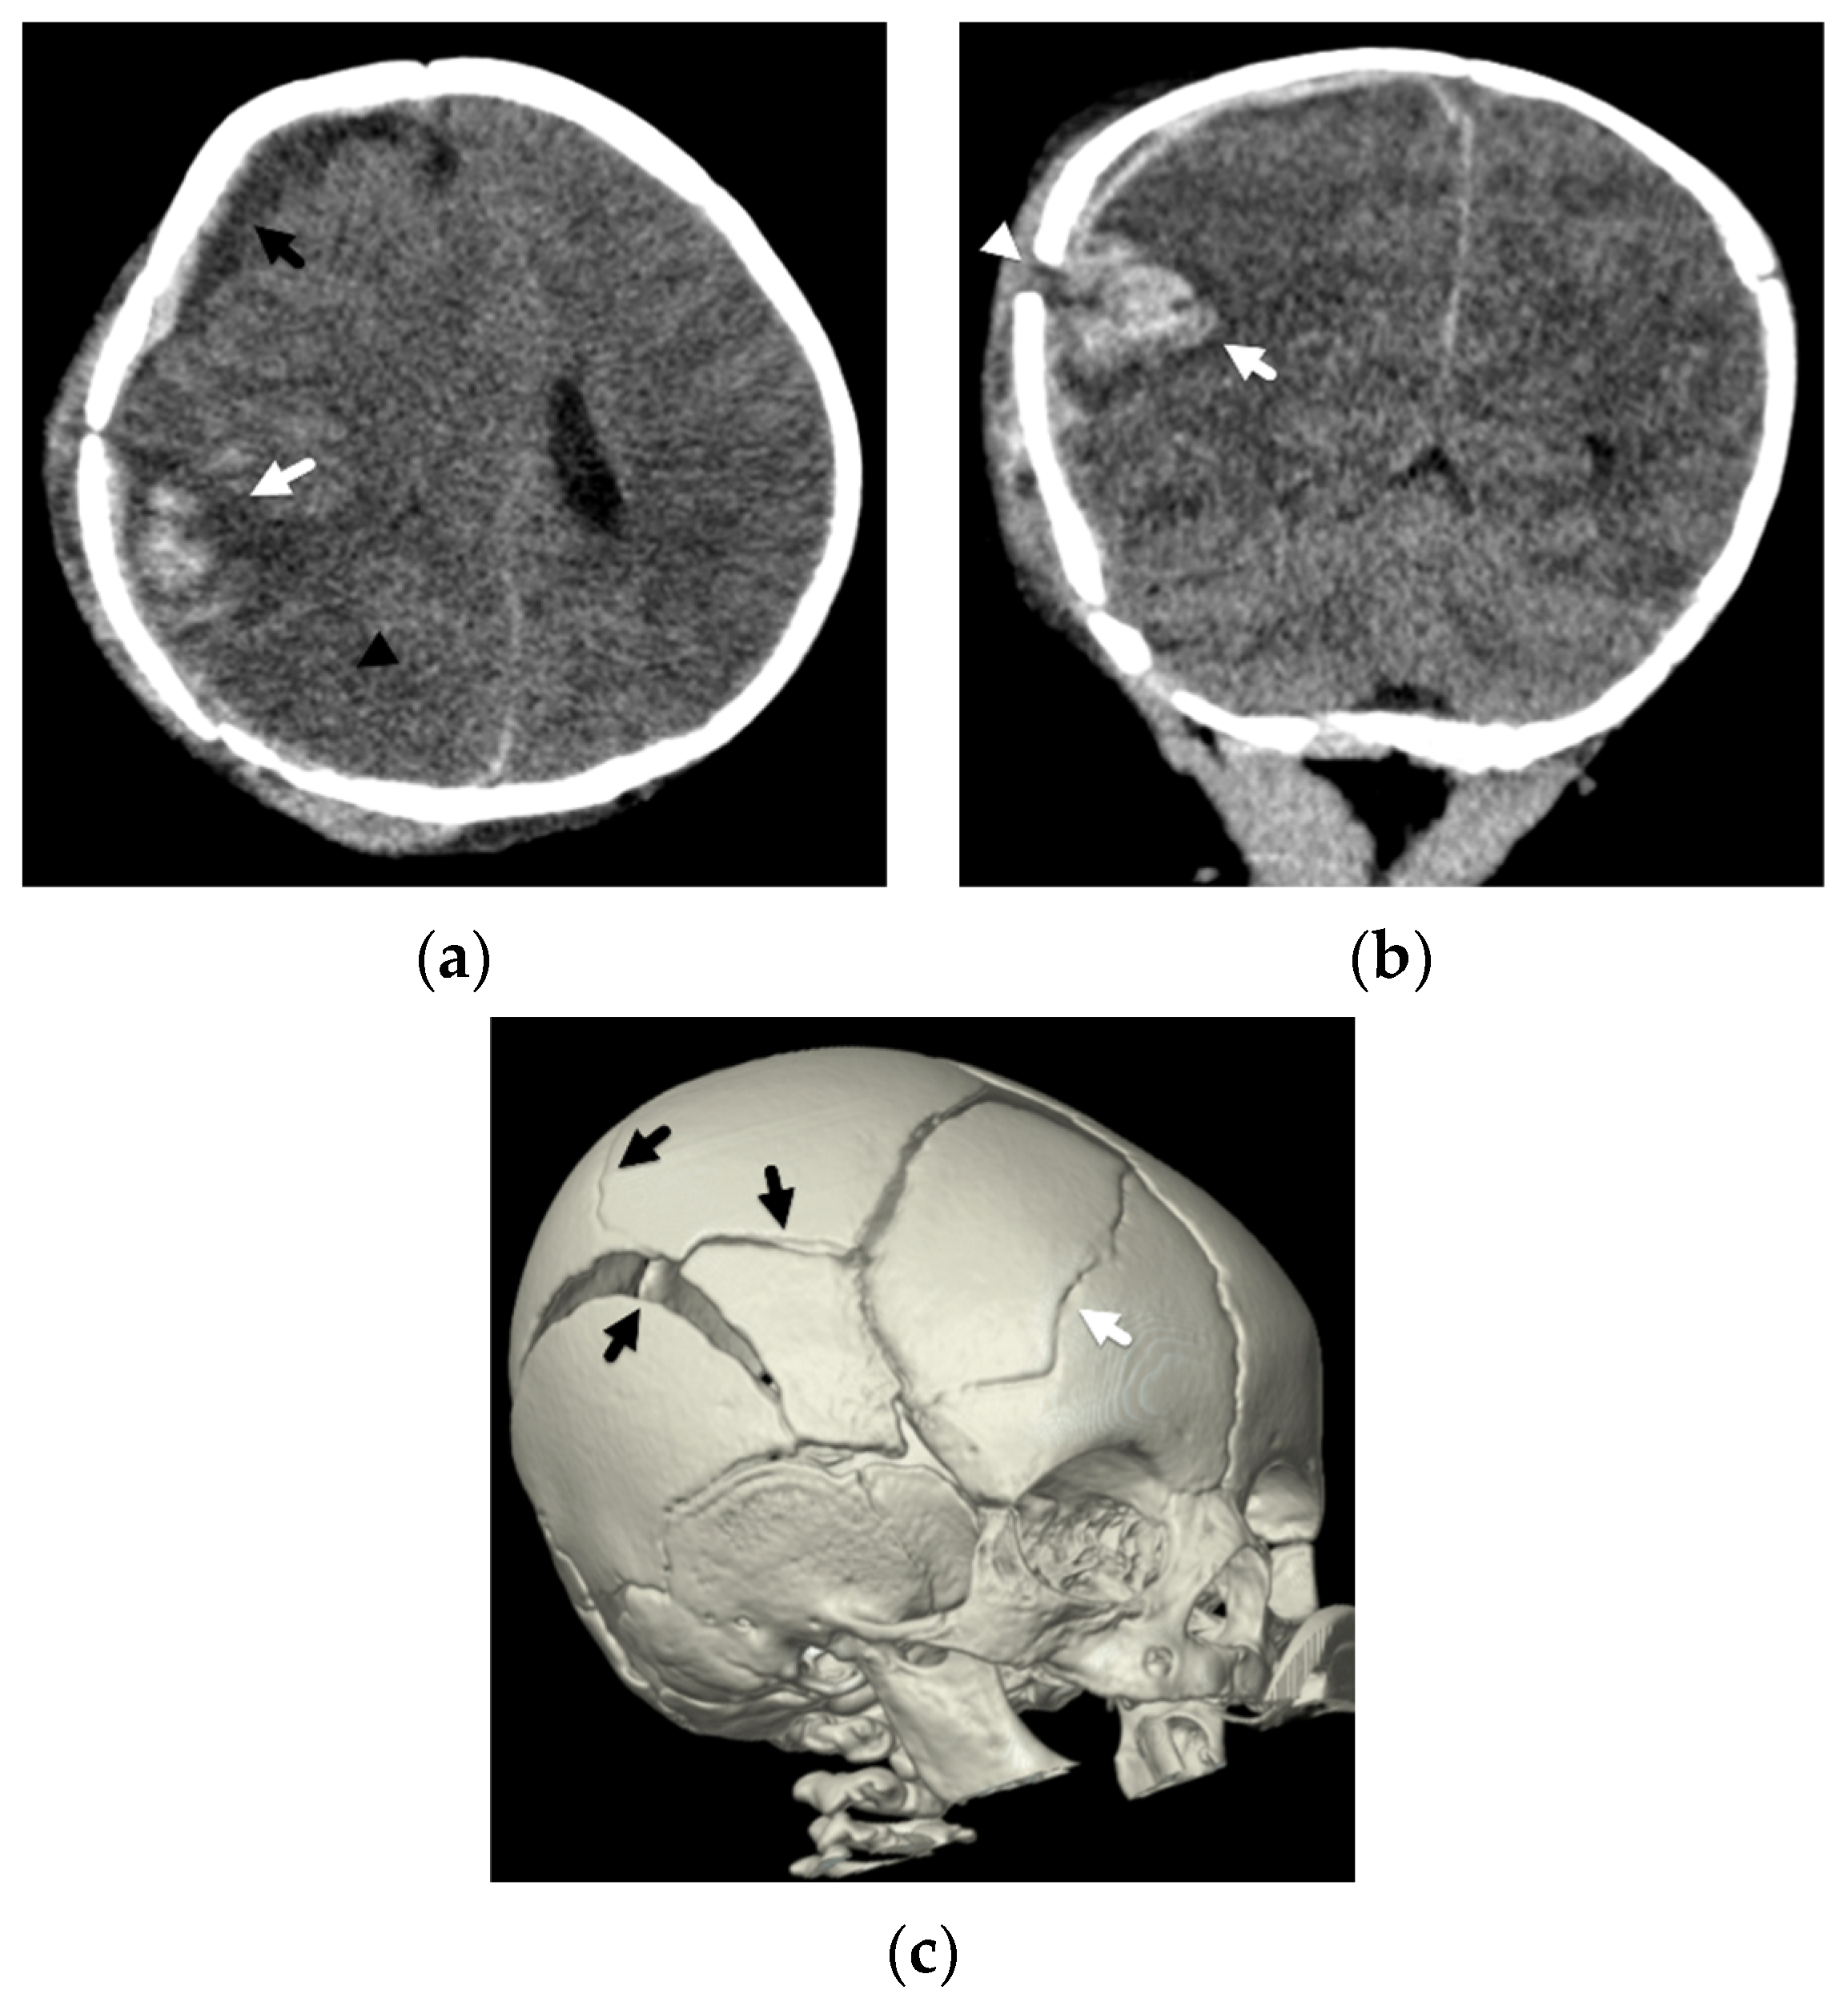

4. Focal Parenchymal Insults

5. Imaging Evaluation